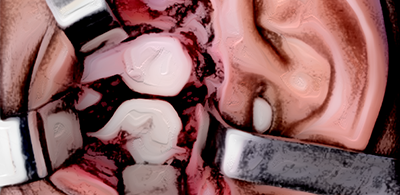

Reconstrução da ATM sem uso de próteses metálicas